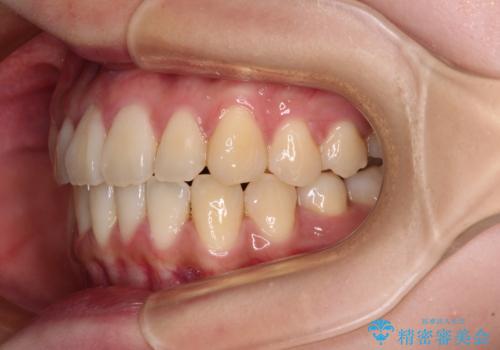

しっかりと装着時間を守ってくださったので、予定通り1年強で治療を終えることができました。